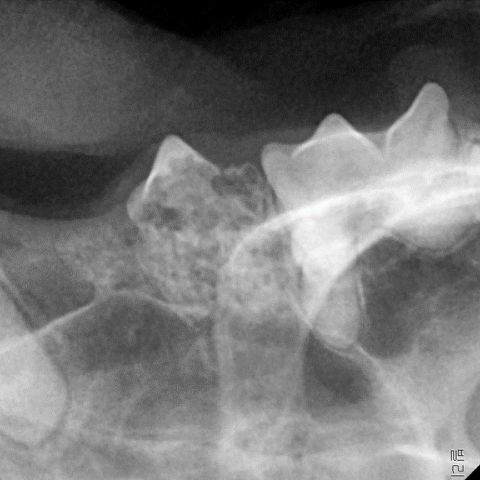

Ä¡¾ÆÈí¼ö¼ºº´º¯ÀÌ »ý±ä Ä¡¾Æ´Â ÆÄÄ¡ ¼¼Æ÷ Ȱµ¿À¸·Î ÀÎÇØ Ä¡¾Æ°¡ ³ì±â ¶§¹®¿¡ À°¾ÈÀûÀ¸·Î Å©±â°¡ À۰ųª Ä¡¾ÆÀÇ ÀϺΰ¡ °á¼Õ µÇ¾î ÀÖ´Â °æ¿ì°¡ ¸¹½À´Ï´Ù. À°¾ÈÀûÀ¸·Î º´º¯ÀÌ ÀÇ½ÉµÉ °æ¿ì Ä¡°ú¹æ»ç¼± °Ë»ç·Î È®ÀÎÇÏ¿© Áø´ÜÀ» ³»¸®°Ô µË´Ï´Ù.

¾à¹° Ä¡·á´Â ±Ùº»ÀûÀÎ Ä¡·á°¡ µÉ ¼ö ¾ø¾î ¹®Á¦°¡ µÇ´Â Ä¡¾Æ¸¦ ¹ßÄ¡ÇÏ´Â °ÍÀÌ °¡Àå È®½ÇÇÑ Ä¡·á¹ýÀÔ´Ï´Ù. ´Ù¸¸ Ä¡¾ÆÈí¼ö¼ºº´º¯ÀÌ »ý±ä Ä¡¾ÆÀÇ °æ¿ì Ä¡¾Æ »Ñ¸®°¡ ÀÌ¹Ì Ä¡Á¶°ñ°ú À¯ÇյǾî ÀÖÀ» ¼ö ÀÖ¾î Ä¡°ú¹æ»ç¼± °Ë»ç ÈÄ ¹ßÄ¡ ¹üÀ§¸¦ °áÁ¤ÇØ¾ß ÇÕ´Ï´Ù.